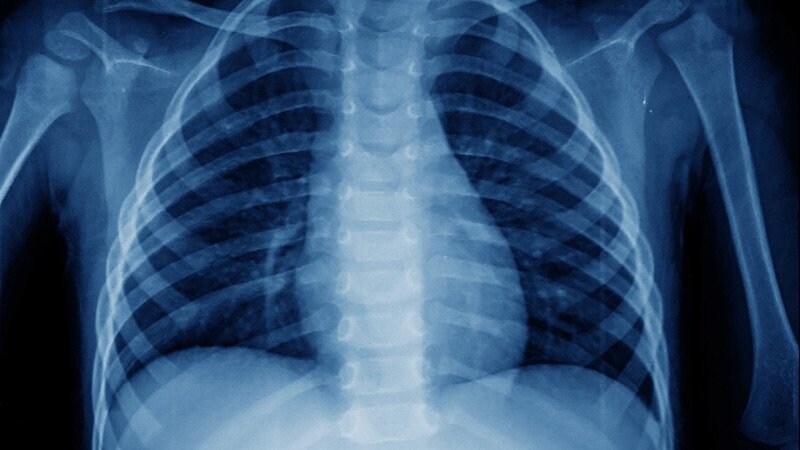

Covid19

O Que Faz A Pneumonia Da Covid 19 Diferente Da Convencional Super